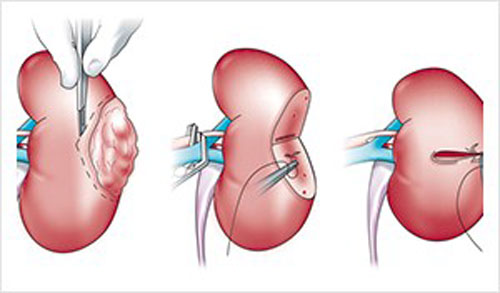

تومور سرطانی کلیه یکی از موذی ترین تومور ها هستند که در اغلب مواقع علیرغم انتشار به مناطق دیگر بدن هیچ علامت و نشانه ای ندارند و در اغلب موارد به صورت اتفاقی و در بررسی ها و چکاب کلیه با سونوگرافی و یا سی تی اسکن.